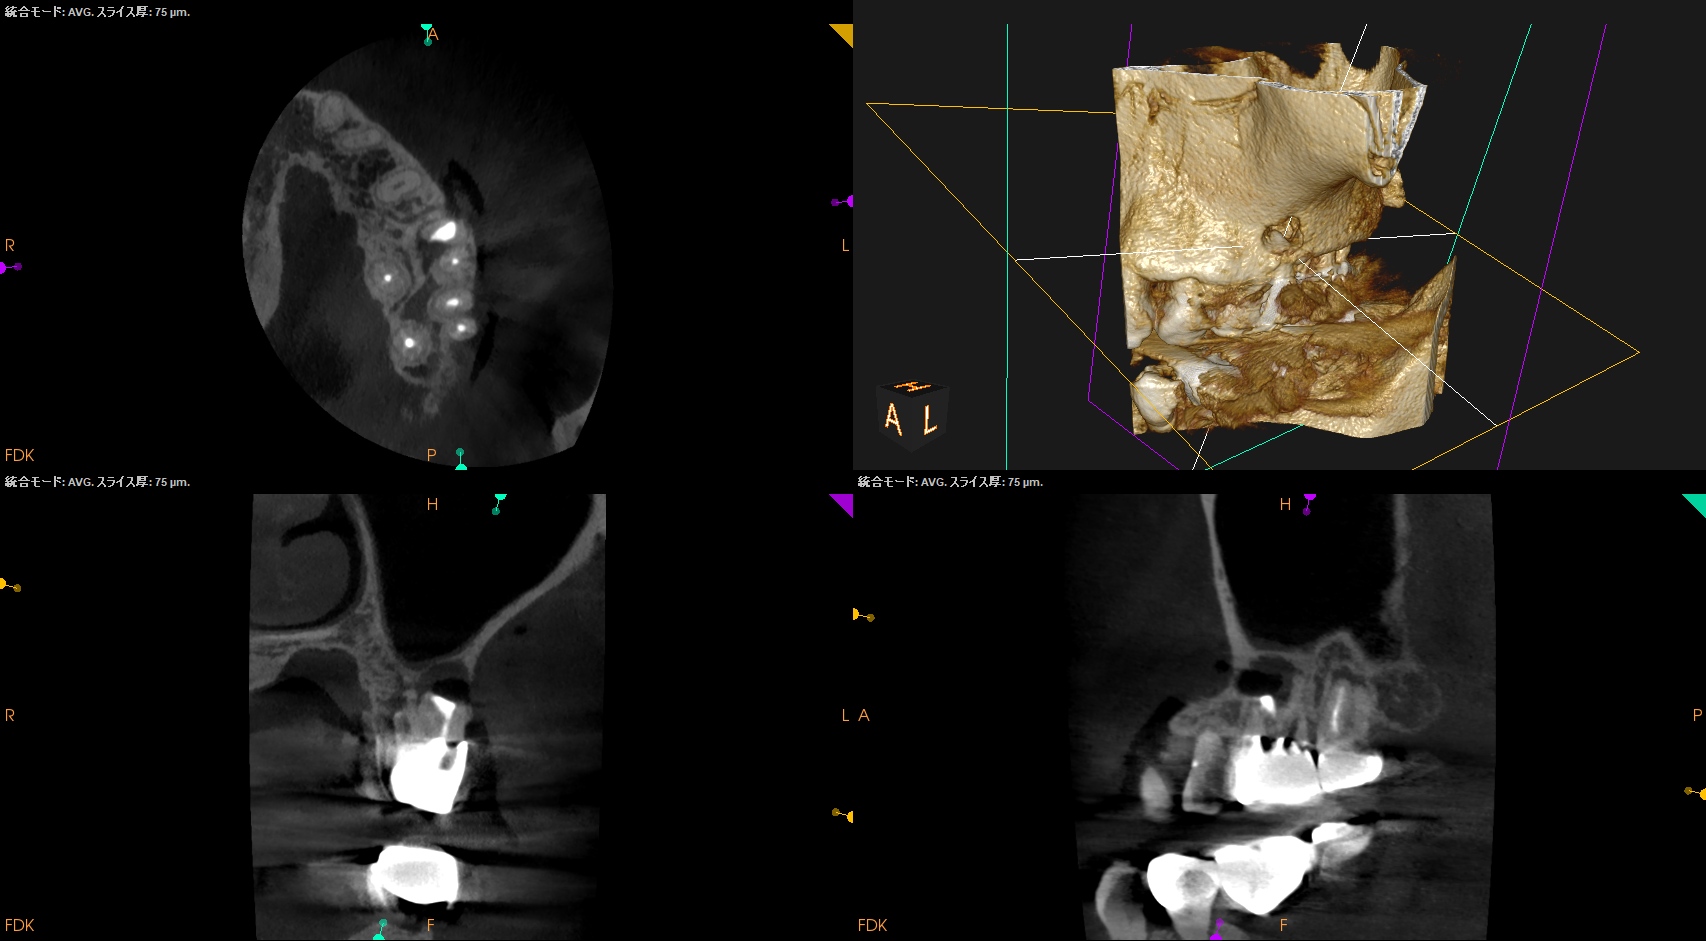

術後にPA, CBCTを撮影した。

後日、築造するがその後のPAが以下だ。

MB

B

逆根管充填材は逆根管形成で穿孔させたが即日修復=充填しているので問題ないだろう。